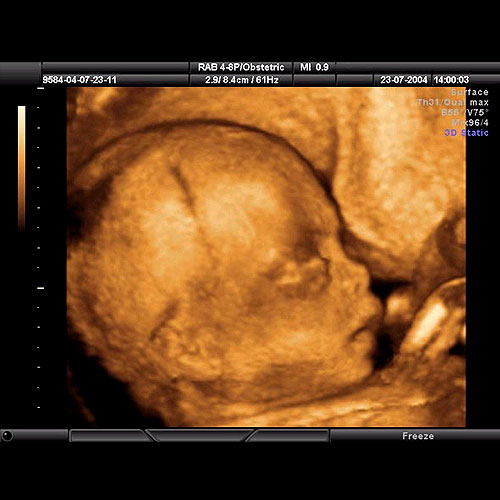

4d Renkli Usg Op Dr Nuh Gumustekin Resmi Web Sitesi Op Dr Nuh Gumustekin Resmi Web Sitesi